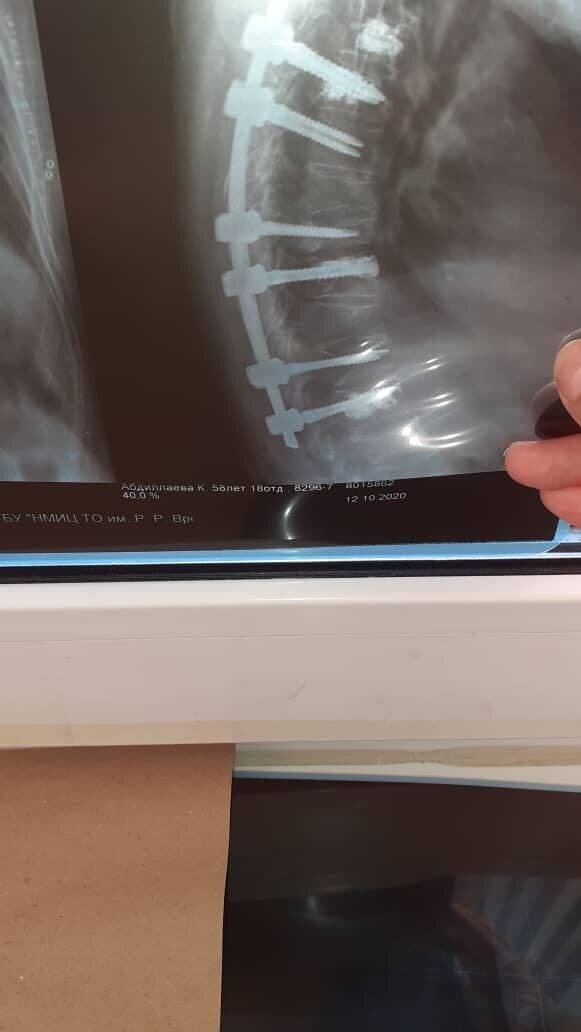

Технологии здоровья

На лечение пациентка легла в НИИ травматологии и ортопедии имени Вредена, а операцию проводил известный хирург, профессор Дмитрий Пташников. Операция была сложной, доктор этого не скрывал, но все прошло удачно. Пациентке выполнили спондилосинтез с фиксацией винтов на цемент и вертебропластику позвонков костным цементом. Позже женщина призналась, что очень переживала и боялась после вмешательства остаться прикованной к инвалидному креслу. Но врачи успокоили: в Петербурге операции на позвоночнике и спинном мозге проходят с использованием интраоперационного нейромониторинга. Аппарат отслеживает нервный сигнал и снижает частоту послеоперационных неврологических осложнений.